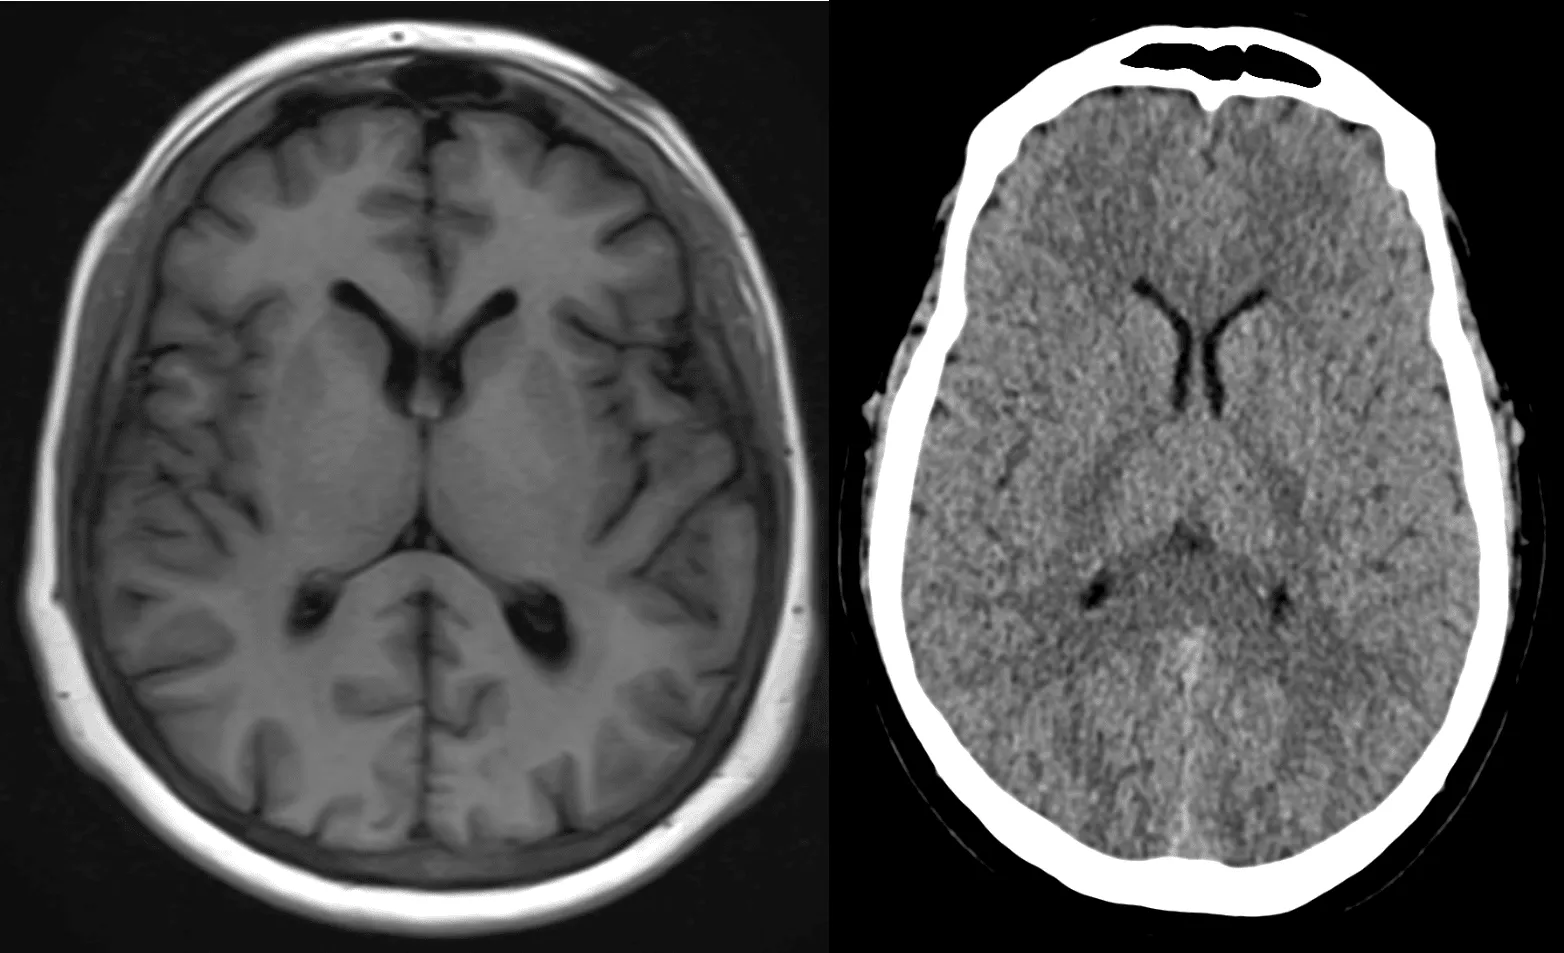

The Structure of the Brain in MRI

The MRI of the brain provides images of various structures within the brain. These include:

1. Cerebrum: The largest part of the brain, responsible for higher brain functions such as thought, memory, sensory processing, and voluntary muscle movements. MRI brain anatomy allows doctors to observe any abnormalities in the cerebrum that might indicate neurological issues.

2. Cerebellum: Located at the back of the brain, the cerebellum is responsible for coordination and motor control. MRI can detect signs of injury or diseases affecting the cerebellum.

3. Brainstem: The brainstem controls vital functions such as heart rate, breathing, and sleep patterns. Abnormalities in the brainstem can be seen through MRI brain imaging, which helps in diagnosing various disorders.

4. Venticular System: MRI scans can also visualize the brain’s ventricles, which are fluid-filled spaces. This is important in identifying conditions like hydrocephalus, where there is an accumulation of cerebrospinal fluid.

5. White Matter and Gray Matter: MRI brain anatomy provides an excellent distinction between white matter (which consists of nerve fibers) and gray matter (where the brain’s processing takes place). Abnormalities in these regions can indicate conditions like multiple sclerosis or dementia.